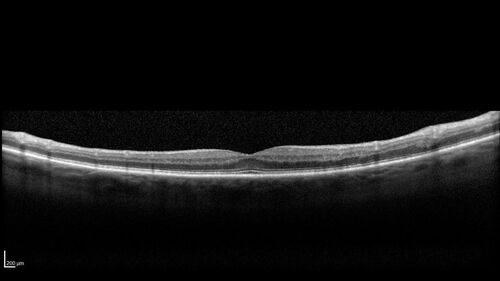

BRVO with good vision

87 year old man with good vision (diabetes without retinopathy). VA 20/25 OU. Vision never worsened from BRVO OS.